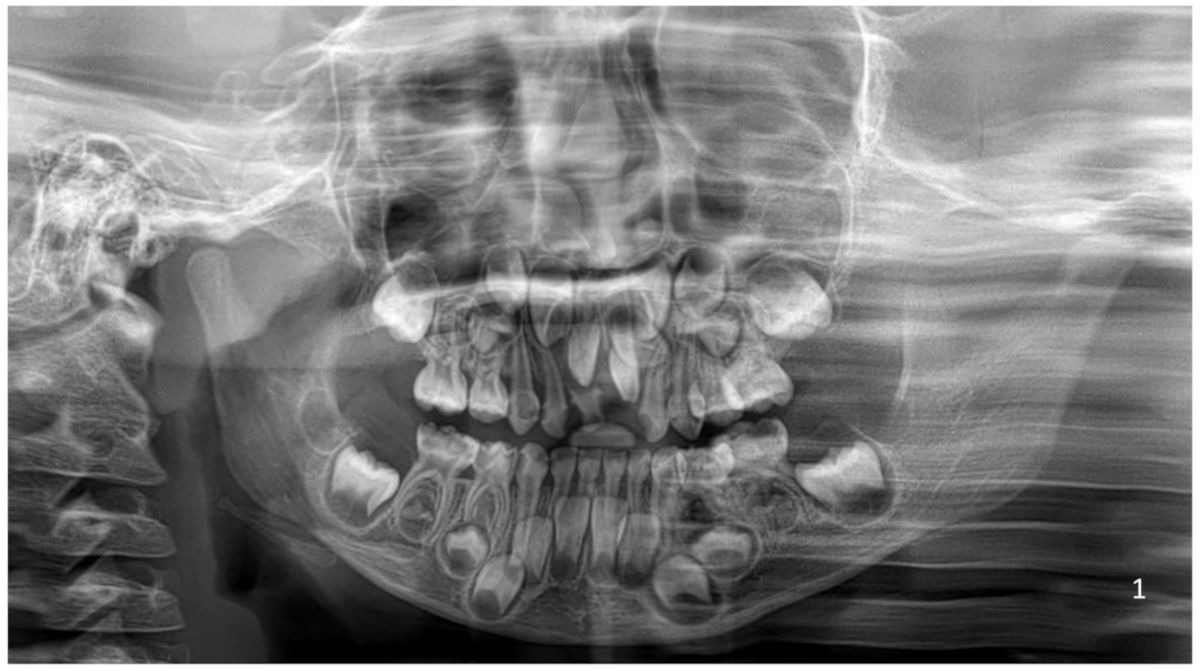

Rare case of a child suffering from a condition called - MEDizzy

image size: 1080x887

Have you ever seen something like this before? It is not edited o. It's a condition where a person develops way more teeth than normal (a rare dental abnormality called hyperdontia). Normally,